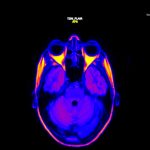

“Headspace” brings the experience of a migraine to life through visuals and sounds. The starting point of the installation is the artist’s personal struggle with the condition. The impulse for creating the piece came from a desire to raise awareness about this disease. After numerous MRI scans the visuals for this piece were created and later evolved into an installation involving sound. These two mediums were chosen because people inflicted by the condition suffer from hypersensitivity towards light and sound. They often experience problems with eyesight or see a halo around objects. Hearing specific sounds creates painful sensations in the head and all over the body. The worst offenders are ticking, sounds created by cutlery, closing and opening doors and also phone notification tones. This can be experienced through the symphony of noise coming from the provided headphones.